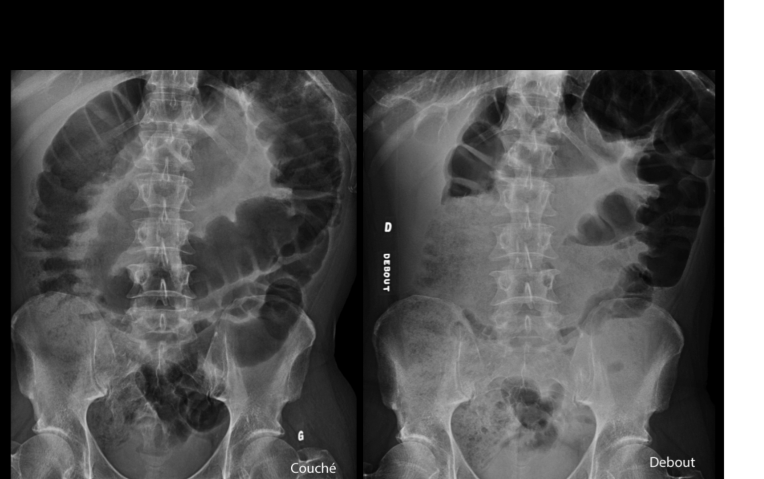

diagnostic?

A

volvulus pck immense